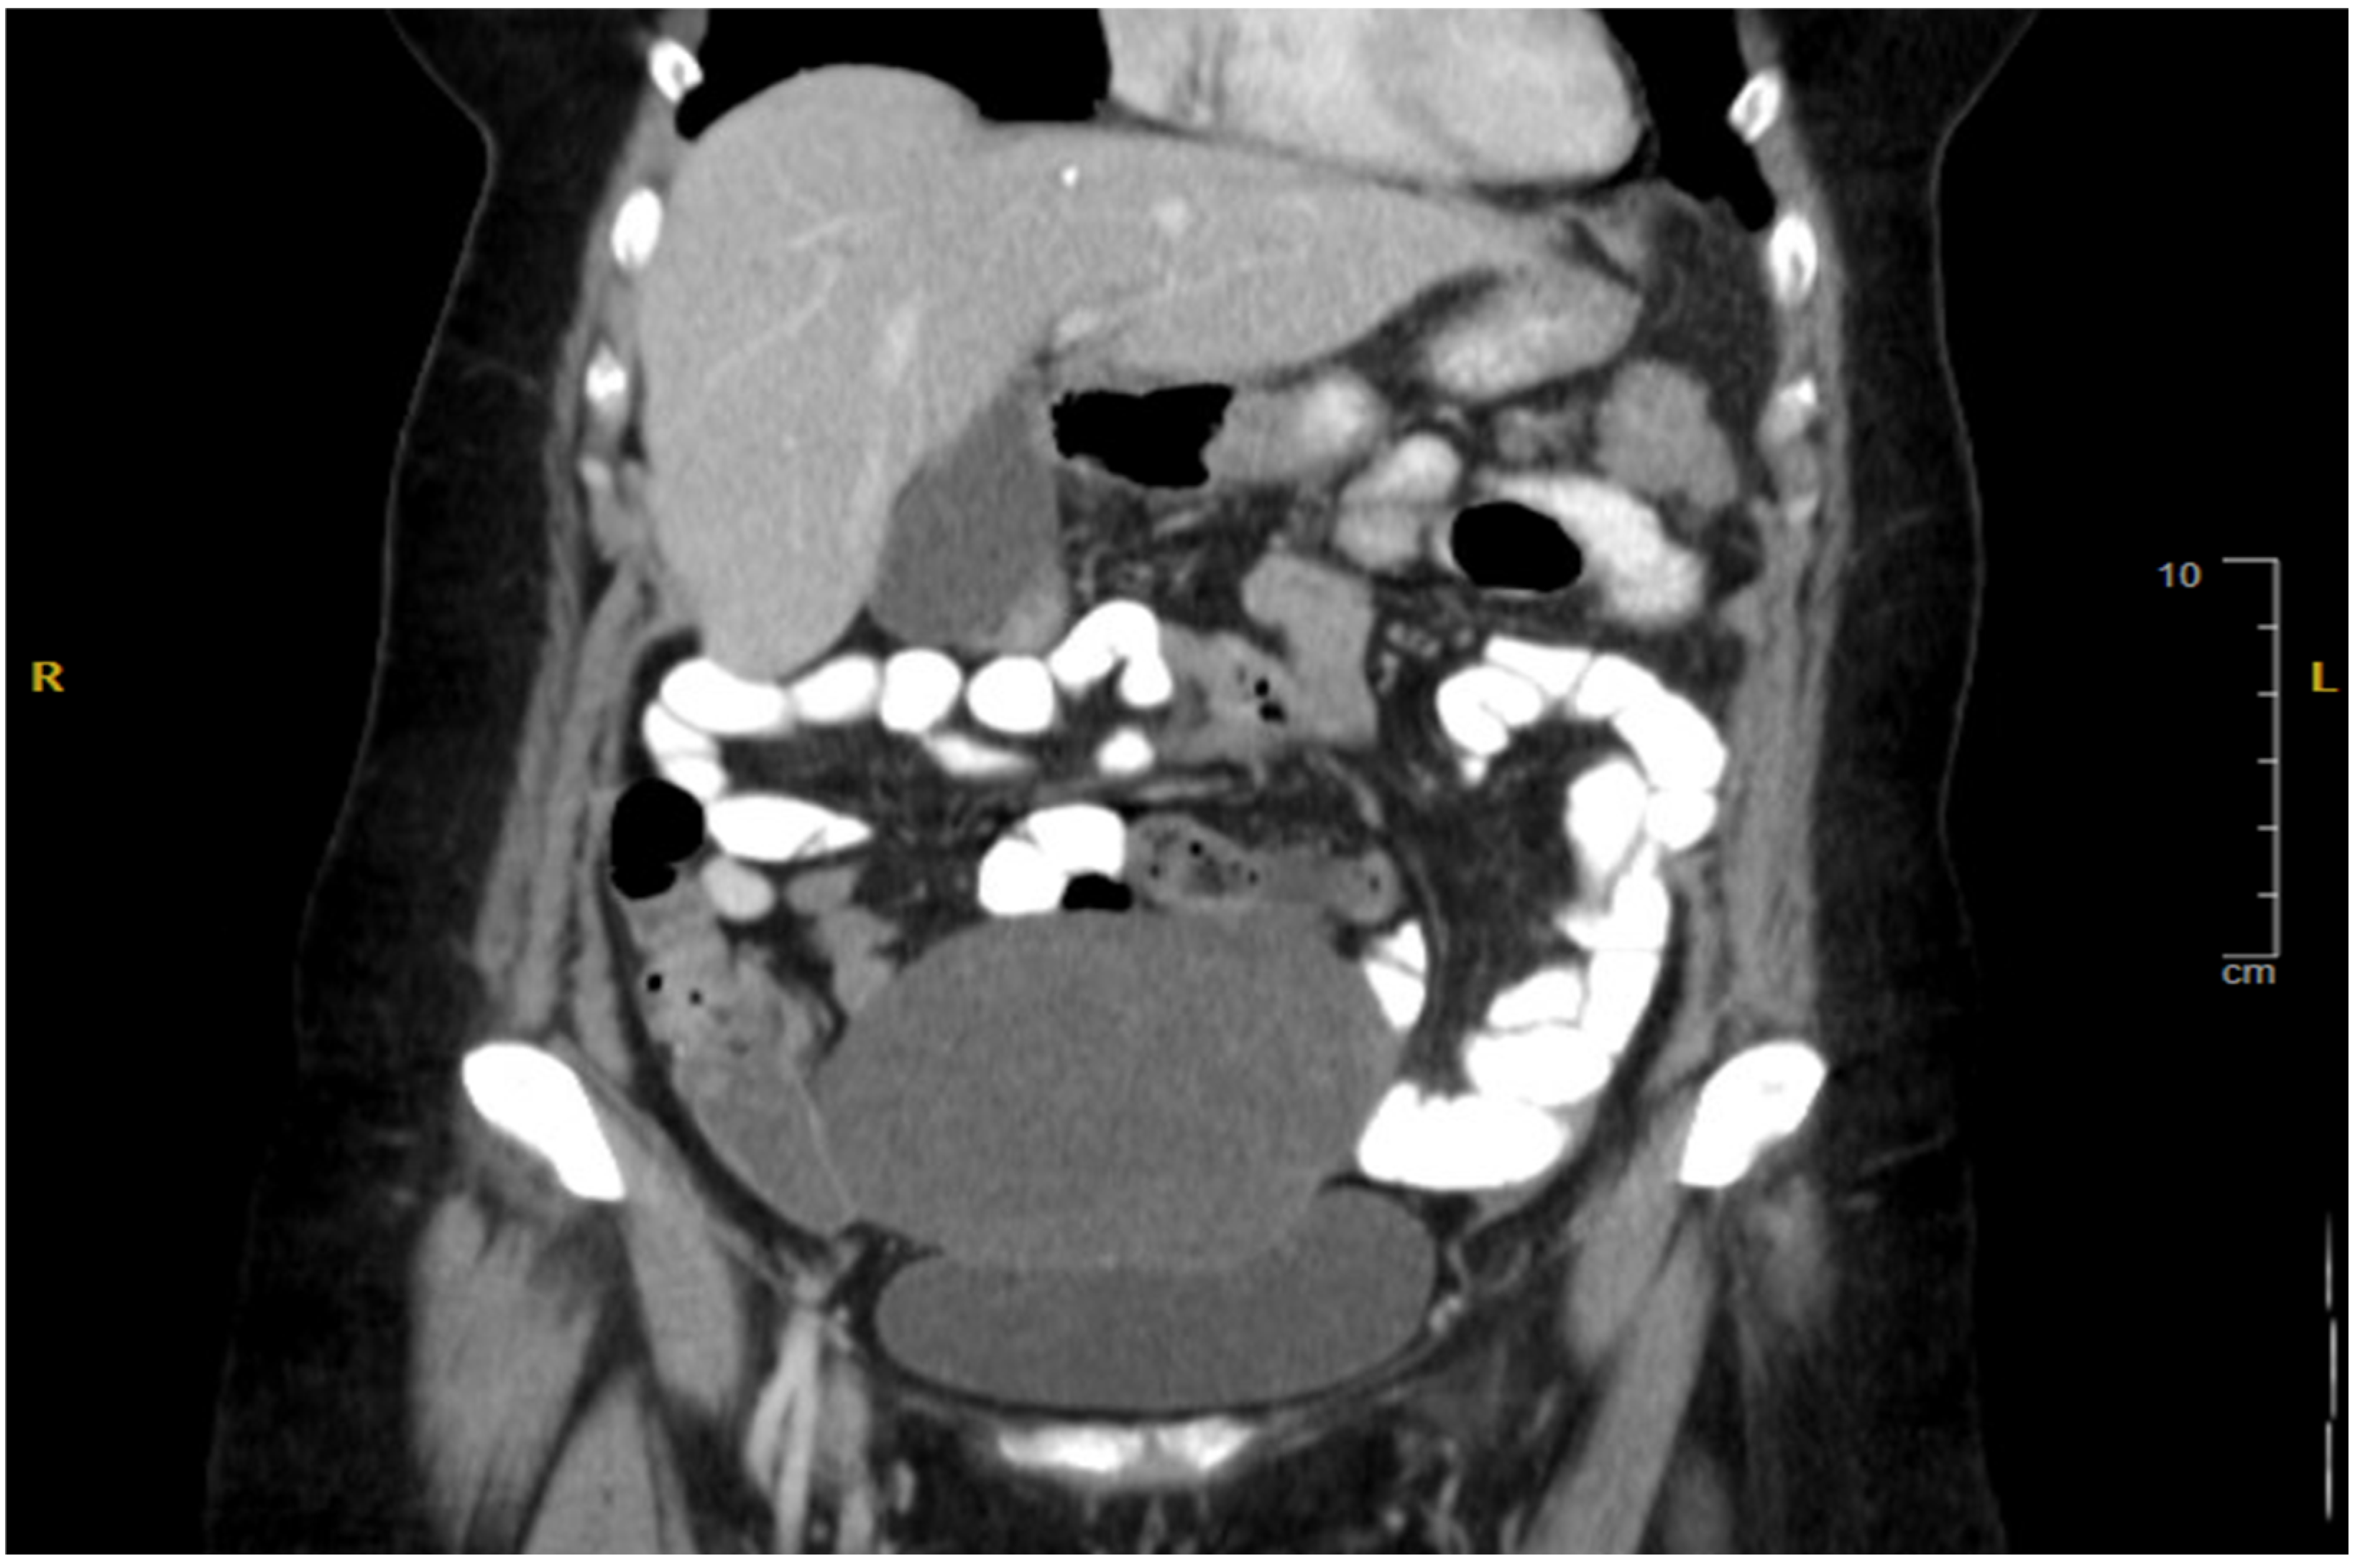

2. Case Presentation